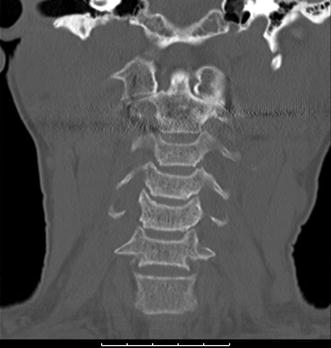

Spondylolisthesis surgery

Spondylolisthesis surgery image This image demonstrates Spondylolisthesis surgery.

Computed axial tomography spine showing proficient reduction of the posterior and the spino-laminar lines and normal canal. The l4 spinal nerve roots exit the skeletal structure cord with the help of diminished bony opening connected the right and the left broadside of our skeletal structure canal.